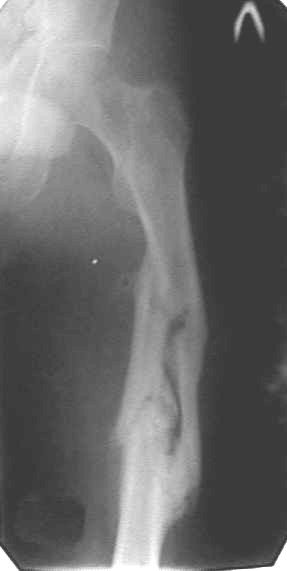

У больного травма 9 месяцев назад. Перелом бедренной кости. Проводилось лечение скелетным вытяжением, гипсовой повязкой. С октября 2001г прекращена иммобилизация. Обратился в нашу больницу в марте 2002г. Имеетсяразгибательная контрактура . Обьем движения в пределах 5 градусов. Предполагается приращение четырехглавой мышцы в области перелома. Планируем проведение операции удлинения сухожилия четырехглавой мышцы.